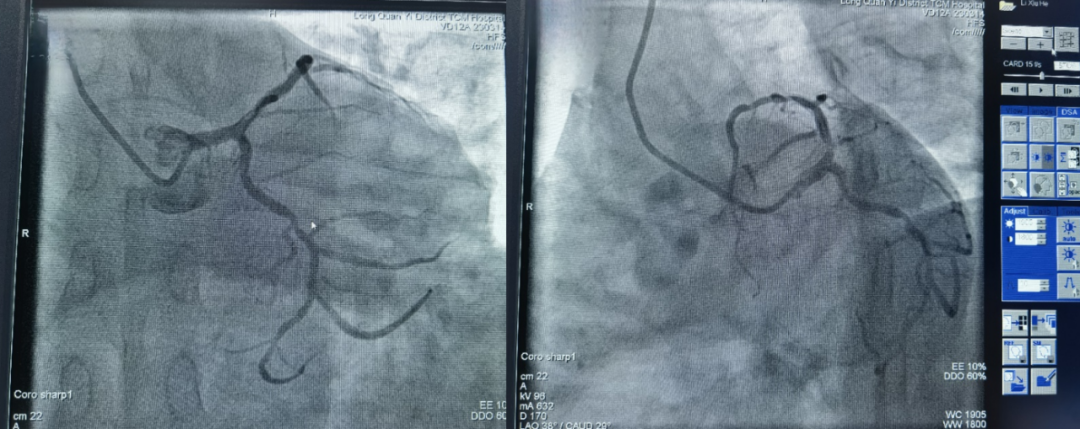

居住龙泉驿的李叔叔,今年55岁,6年前因为心肌梗死在外院做了冠脉支架植入,因交通不便利一直未去复查造影。近两年总觉得胸口憋闷不舒服,稍微活动就心累、气喘,情绪激动还有胸痛症状。

李叔叔一直害怕是支架堵塞,但又苦于儿女远在外地,不方便去复查。最近听说家门口的龙泉中医院可以做心脏介入手术,赶忙前往我院内三科(心血管科)办理住院。

完善术前检查后,主管医生张医生为其安排了冠脉介入手术,由成都中医药大学附属医院派驻我院的张德来副院长为其行冠脉造影术。手术顺利,李叔叔平安返回病房,悬着的一颗心也总算放了下来。